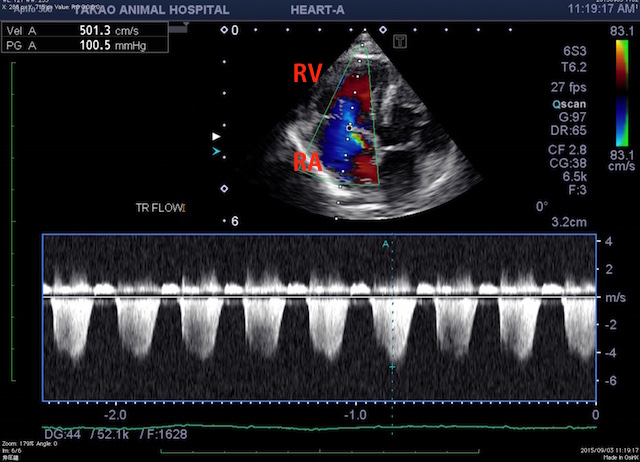

(RV:右心室 RA:右心房)

右心房に逆流する血液の流速から収縮期の肺動脈の血圧が分かるのですが、おおよそ110mmHg位あります(正常は20mmHg程度)。この症例の血圧は収縮期が80mmHgでしたので、完全に右心室と左心室の血圧が逆転しています。